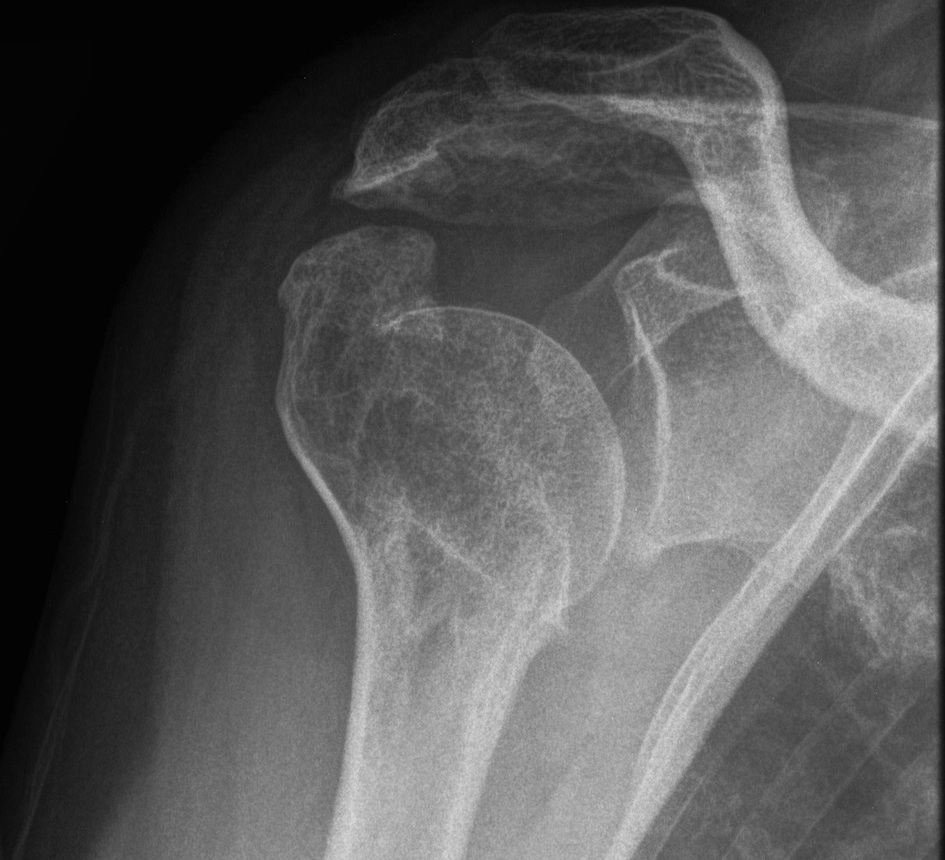

proximal humerus fracture Background ORIF with locking plate Arthroplasty Greater tuberosity fractures Lesser tuberosity fractures / avulsions Book traversal links for Proximal humerus fractures ‹ Pectoralis Major Tears Up Background ›